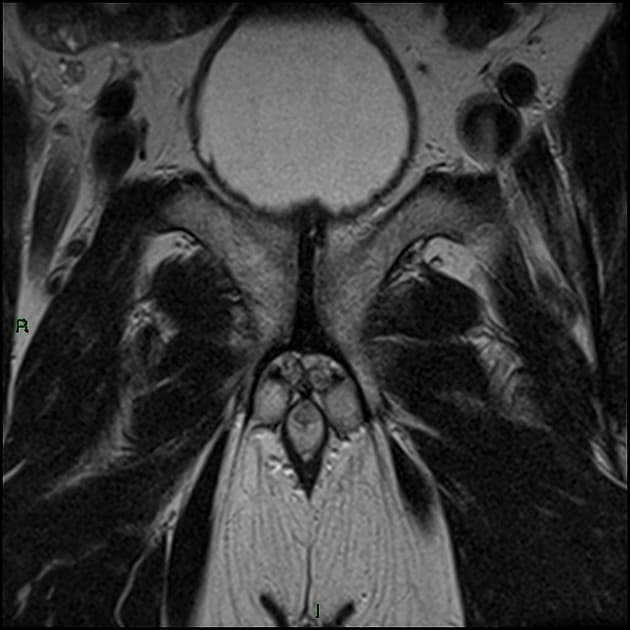

Chụp cộng hưởng từ đa tham số (mp MRI) tuyến tiền liệt (prostate)

- MRI đa mặt phẳng (multiplanar MRI) cho thấy một nốt vùng đỉnh phía trước (anterior apical nodule) thuộc vùng chuyển tiếp (transition zone), giới hạn không rõ (ill-defined), có hạn chế khuếch tán (restricted diffusion) và ngấm thuốc sớm mạnh (early avid enhancement).

Ung thư tuyến tiền liệt (Prostate cancer) - nốt vùng đỉnh (apical nodule) PI-RADS 3

Trường hợp này trình bày một tổn thương PI-RADS 3 ở vùng chuyển tiếp phía trước vùng đỉnh, ban đầu bị bỏ sót bởi sinh thiết TRUS nhưng sau đó được xác nhận là ung thư biểu mô tuyến thông qua sinh thiết dưới hướng dẫn MRI. Ca lâm sàng nhấn mạnh tầm quan trọng của MRI đa tham số (mpMRI) và PSMA PET trong việc xác định các tổn thương nghi ngờ. Theo PI-RADS v2, chuỗi xung chủ đạo của vùng chuyển tiếp là T2W, trong khi vùng ngoại vi dựa vào DWI. Sinh thiết đích trong máy MRI là công cụ quan trọng để tiếp cận các tổn thương ở vị trí khó như vùng đỉnh, nơi mà sinh thiết TRUS tiêu chuẩn có thể thất bại.